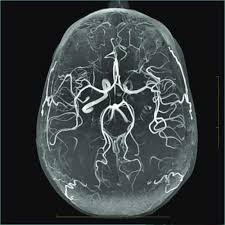

"MRA(Magnetic Resonance Angiography, 자기공명 혈관촬영)"는 MRI를 기반으로 혈관 구조를 영상화한 검사입니다.

- 원리: MRI 기술을 활용하여 혈류 신호를 강조하고, 혈관과 주변 조직을 분리하여 영상화

- 주요 특징: 동맥, 정맥, 혈관 협착, 동맥류 등 혈관 상태 평가에 특화

- 조영제 사용 여부: 일부 경우 가돌리늄 기반 조영제를 사용해 혈류를 더 명확하게 관찰

MRA는 심혈관 질환, 뇌혈관 질환, 말초 혈관 질환 등 혈관 이상 진단에 특히 유용합니다.

- 뇌혈관 질환: 동맥류, 뇌경색 위험 평가